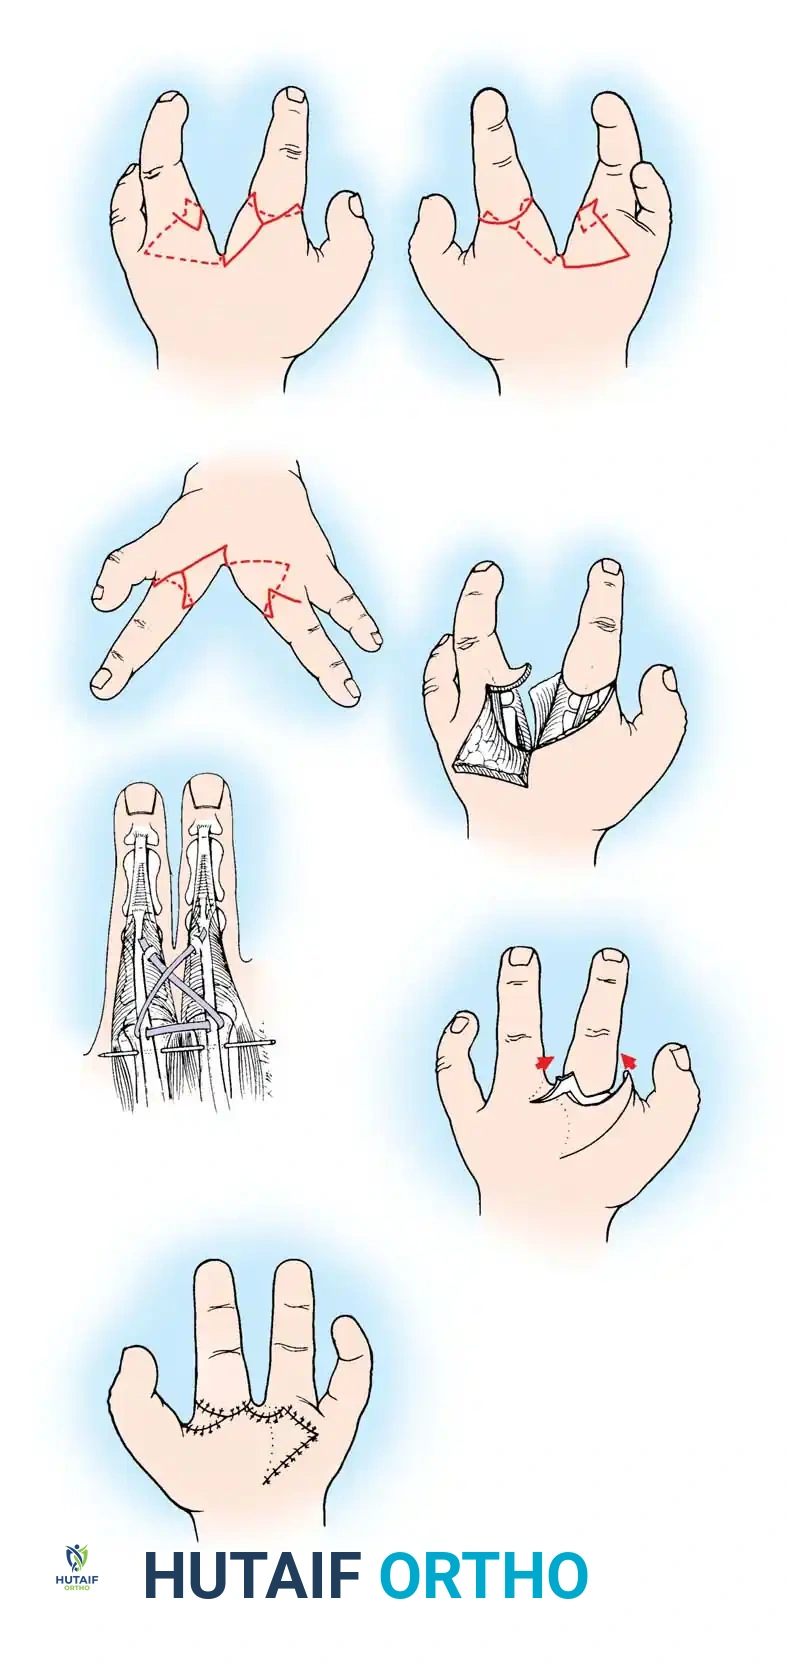

Fig. 76-2 Failure of formation (digital nubbins). The presence of functional wrist motion allows the limb to be used effectively as an assisting hand.

Hypoplasia of the more proximal musculature is a key clinical finding that helps differentiate true transverse deficiencies from amputations caused by congenital constriction band syndrome (amniotic band sequence). In the most common presentation—the upper forearm amputation—the forearm is usually no more than 7 cm long at birth and will reach a maximum length of approximately 10 cm by skeletal maturity.

In midcarpal amputations (the second most frequent level), the rudimentary digital remnants are almost always nonfunctional. However, because the radiocarpal joint is preserved, pronation and supination are usually possible, providing a highly functional assisting limb. Cognitive development and intelligence in these children are generally normal.